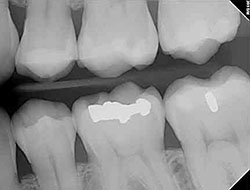

Fillings

Traditional dental restoratives, or fillings, may include gold, porcelain, or composite. Newer dental fillings include ceramic and plastic compounds that mimic the appearance of natural teeth. These compounds, often called composite resins, are typically used on the front teeth where a natural appearance is important. There are two different kinds of fillings: direct and indirect. Direct fillings are fillings placed directly into a prepared cavity in a single visit. Indirect fillings generally require two or more visits. These fillings include inlays, onlays, veneers, crowns, and bridges fabricated with gold, base metal alloys, ceramics, or composites.